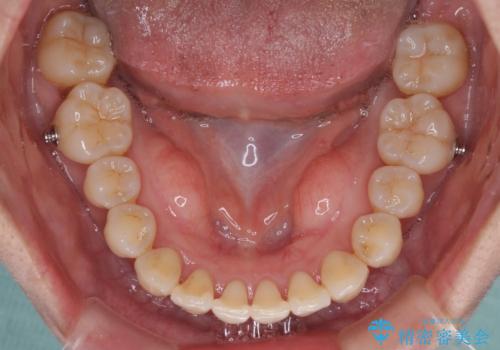

インビザラインでの矯正治療を希望されていましたが、奥歯の咬み合わせがインビザライン単独では改善困難と判断されたので、補助装置を併用することとしました。

上顎最後臼歯は極端に外側を向いており、下顎骨に対して上顎骨が前方に位置していたため、補助装置により最後臼歯を一気に内側に引き込むとともに、上顎臼歯を後方移動させ、奥歯の咬み合わせが改善した後に、上下インビザラインにより歯列全体を整えていくこととしました。

奥歯の咬み合わせを事前に望ましい位置に改善したことで、インビザライン単独では改善が最も困難な状況を排除することができ、非常に理想的な仕上がりとなりました。